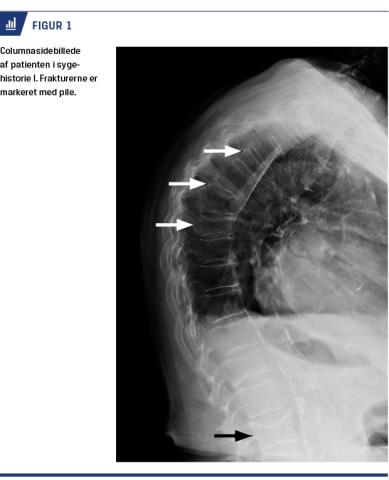

injektion i september 2016 blev indlagt med dehydrering, hypoparatyroid hyperkalcæmi og svært nedsat nyrefunktion sekundært til diarré fik hun ikke injektionen. Ved udredning afkræftedes malignitet, og efter rehydrering blev hun udskrevet med habituelle biokemiske værdier. I marts 2017, et år efter sidste injektion af Dmab, fik hun spontant nytilkomne rygsmerter, og en røntgenoptagelse af ryggen viste nye frakturer i TH4, TH6 (nu totalt sammenfaldet) Th8 og L3 (alle ≥ 50% sammenfaldne) (Figur 1).